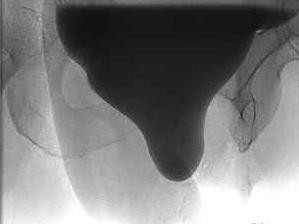

Rekonstruktive Beckenbodenchirurgie: So haben Sie Komplikationen im Griff

Die rekonstruktive Beckenbodenchirurgie bietet vielfältige operative Optionen bei Harninkontinenz, Organprolaps und weiteren Beckenbodenstörungen. Für den Therapieerfolg sind eine präzise Diagnostik, konservative Alternativen sowie interdisziplinäre Expertise entscheidend – denn das Komplikationsmanagement beginnt bereits vor dem Eingriff.

Bildnachweise